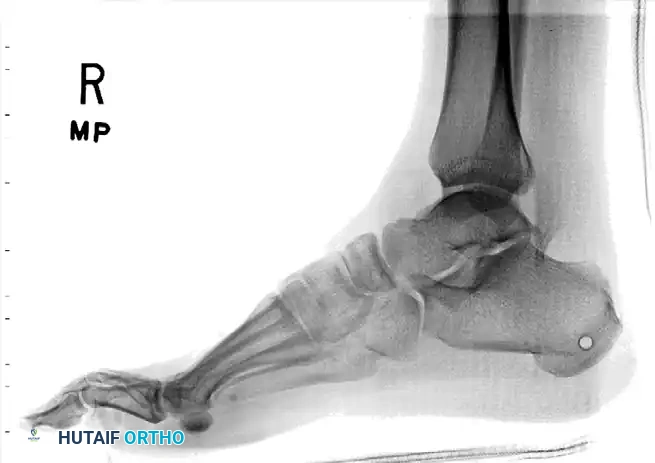

Standard trauma radiographs of the ankle (AP, lateral, and mortise) and foot (AP, lateral, and oblique) are required.

Radiographic appearance of a medial subtalar dislocation. The talonavicular and talocalcaneal joints are completely disrupted.

Radiographs demonstrating a lateral subtalar dislocation before and after reduction.